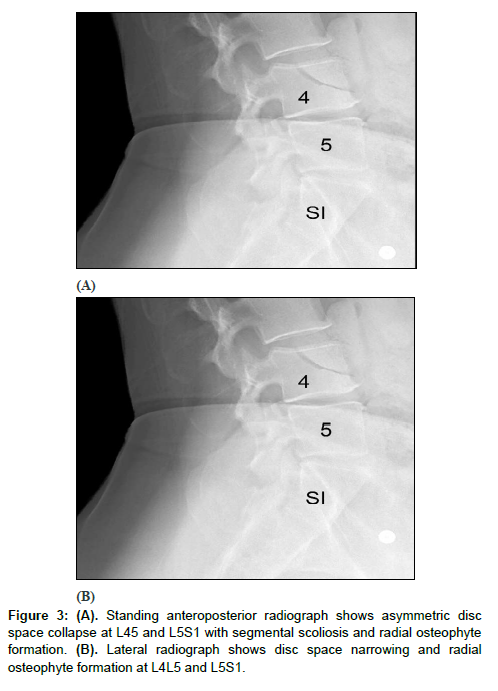

All patients showed successful radiographic fusion six months after surgery with evidence of bridging trabecular bone across the interspace forming a continuous bony connection from the superior vertebral body to the inferior vertebral body (Figures 1 and 2). In addition, there was no evidence of radiolucency involving more than 25% of the superior or inferior implant-vertebral interface. No patients had deterioration in their fusion status between the six-months and the last follow-up; all patients remained fused. There was no evidence of implant migration, subsidence, or loss of segmental lordosis at any disc level studied. There were no radiographic fusion differences in patients treated with one- or two-level fusion surgeries (Figure 3 and 4). Similarly, there were no differences in fusion outcomes regarding the PLIF or XLIF surgical approaches.

Figure 4: (A). Anteroposterior radiograph shows correction for the segmental scoliosis. (B). Lateral radiograph shows improved segmental lordosis at L4L5 and L5S1and no evidence of interbody implant subsidence. (C and D). Dynamic flexion and extension lateral radiographs show no motion across the fused interspaces and no interbody implant subsidence.